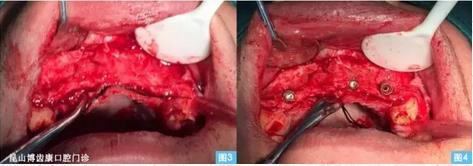

圖3圖4:(左圖3)牙槽嵴頂偏腭側(cè)水平切口,雙側(cè)附加切口翻開全厚粘骨膜瓣至鼻底,清晰暴露術(shù)區(qū)。(右圖4)小球鉆定位,擴(kuò)孔鉆依次備洞,植入植體 ,可見13、23唇側(cè)骨壁缺損嚴(yán)重 。

圖5圖6:在骨缺損區(qū)周圍用小球鉆制備多個(gè)營(yíng)養(yǎng)孔(可為骨再生提供良好的血運(yùn))將生理鹽水與骨替代材料混合后覆蓋于骨缺損區(qū),再放置鈦膜,再修剪生物膜覆蓋于i-Gen鈦膜上。骨增量以后原有的軟組織量不足,需要增加軟組織的游離度,在唇側(cè)粘膜瓣底做減張切口,無(wú)張力的關(guān)閉牙槽脊頂?shù)那锌冢ㄖ踩肱ち?5牛 50轉(zhuǎn))。